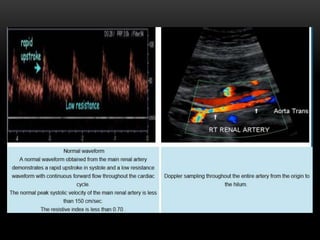

Normal renal arteries demonstrate low resistance waveforms – R I <

0.7.

A low resistance waveform with sharp systolic upstroke is expected in the normal main

renal artery (A).

The early systolic peak (ESP) (arrow) is seen as a small notch in systole in the normal

intrarenal arterial waveform. The systolic upstroke is rapid with an acceleration time of

0.07 seconds or less.

Normal Doppler waveforms obtained from the main renal artery and segmental renal artery